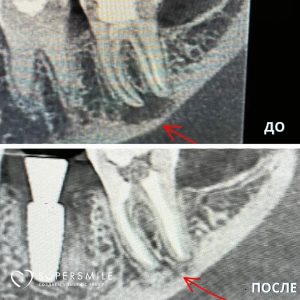

Диагностика

Для постановки точного диагноза и дифференциальной диагностики, доктор направляет вас на рентгенологическое обследование, в некоторых случаях необходима КТ-диагностика. Затем оценивает результат и назначает дальнейшее лечение.

Обтурация (пломбирование) корневых каналов

Корневые каналы тщательно высушивают специальными бумажными пинами (турундами) и обтурируют (пломбируют). Чаще всего для обтурации используют гуттаперчевые штифты и силер (специальная паста для пломбирования корневых каналов). Но также в нашей клинике вы найдете применение разогретой или термопластифицированной гуттаперчи. После пломбирования корневых каналов обязательна рентгенологическая диагностика качества обтурации корневых каналов.

Работы наших специалистов по лечению каналов зуба